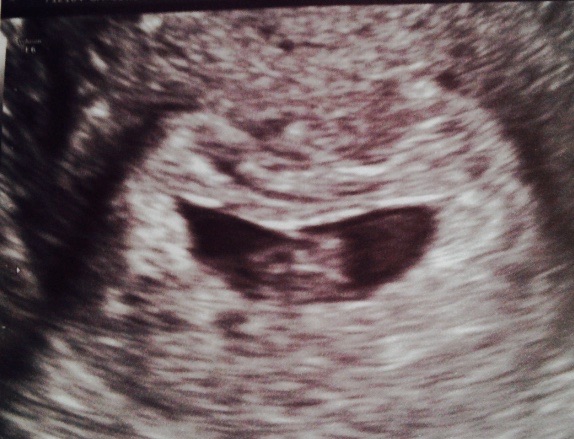

Had our first u/s this morning. Everything went well! Baby H had a 138 hr and is measuring closer to 7wk0d than 9wk3d. I figured this would be the case because of my longer cycles. We go back in two weeks for a dating sonogram to get a better EDD. Currently I'm July 28 instead of the 7th! Also confirmed there's only ONE baby in there! All good news here! Yay!